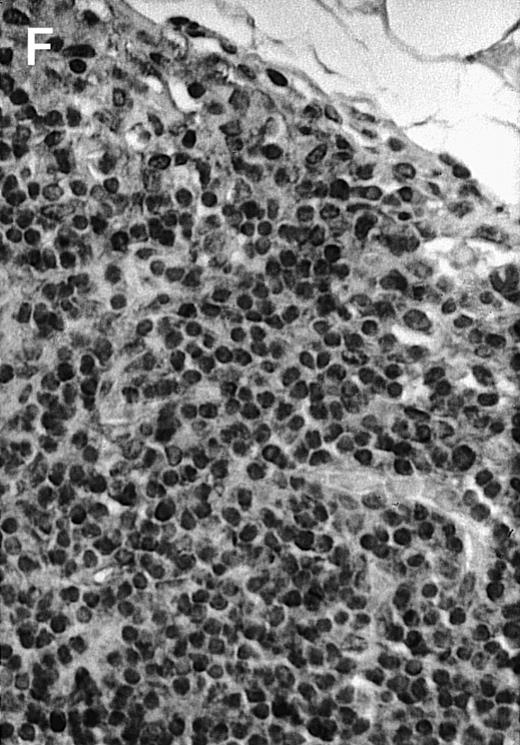

To explore the mechanisms of the protection from BCL growth, histologic analysis was performed on tumor tissue from mice treated with ST40L, ST, or PBS alone. In the mice treated with PBS alone, no cellular infiltrate expressing FasL was observed in the surrounding tissues and inside the BCL region (Figure 4A and D). In contrast, infiltrating lymphocytes expressing FasL were observed around the vessels and also scattered in the smaller tumor tissues in the mice treated with ST (Figure 4B and E). Small hard nodules (2-5 mm in diameter) were observed at the SC injection sites of the long-term survival mice that had been treated with ST40L. On histologic analysis, these small nodules were confirmed to be the result of an accumulation of lymphocytes, and not BCL cells (Figure 4C). These lymphocytes were also found to be strongly positive for FasL expression (Figure 4F). On the other hand, lymphocytes infiltrating in the nodules were stained by either CD4+ Ab or CD8+ Ab, but the ratio of CD4+ and CD8+ cells was not 1-sided (data not shown).

Histologic analysis of A20 tumors excised 21 days postchallenge from BALB/c mice immunized with ST40L.

(A) HE stain of a BCL region in a mouse treated with PBS alone. (B) HE stain of a smaller BCL region in a mouse treated with ST. (C) HE stain of a small hard nodule at the SC injection site in a mouse treated with ST40L. (D) Fas ligand staining of a BCL region in a mouse treated with PBS alone. (E) Fas ligand staining of a BCL region in a mouse treated with ST. (F) Fas ligand staining of a small hard nodule at the SC injection site in a mouse treated with ST40L. Original magnifications are ×400.

When A20 cells were stimulated with NIH3T3/CD40LT, Fas expression was found to be up-regulated in vitro. CD40 ligation induces Fas expression on cells and facilitates apoptosis through the FasL/Fas pathway.36 Fas is not always expressed on malignant B cells, but CD40 ligation leads to an up-regulation of Fas antigen and enhances sensitivity to the Fas-mediated death signal in vitro.37 38 ST40L was found to trigger the infiltration of FasL expressing lymphocytes into the BCL tumors, with the degree of infiltration being associated with tumor regression, thus suggesting that ST40L might elicit a strong antitumor immunity via up-regulating Fas on A20 cells and amplifying T cells expressing FasL in tumor.